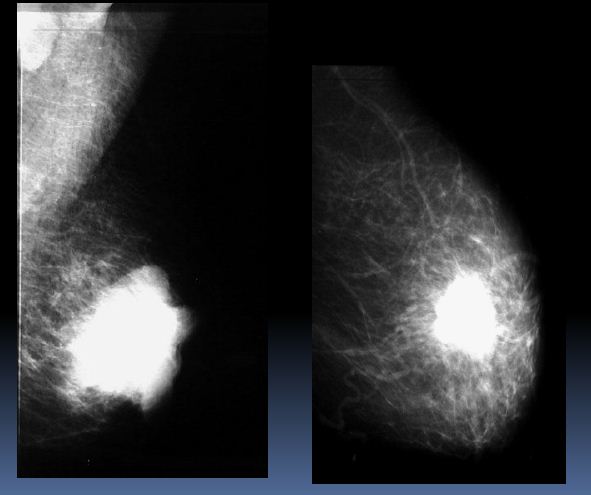

Ca prsu

Kazuistika 1

- Klientka vyšetřena v 2006, MMG+UZ – bez ložiskových změn

- MDL dx – technicky nesprávná

- Následně vyšetřena 2009 s nálezem léze v HQ dx preaxilárně